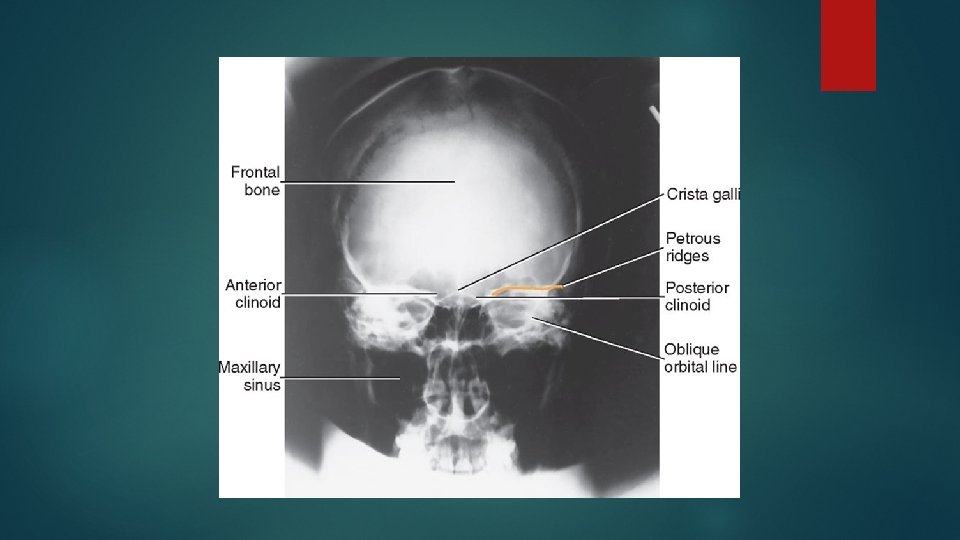

Occipito frontal view Positioning of patient : Patient is seated facing the erect bucky, so that the median sagittal plane is with the midline of the bucky and perpendicular to it. Neck is flexed to bring orbito meatal line perpendicular to the bucky, this can be achieved by ensuring the nose and forehead are in contact with the bucky.

Central ray : Ray is directed perpendicular to the bucky along the median sagittal plane and at the level of nasion. Image should include the vertex superiorly and base of occipital bone inferiorly

Caudal angulation : OF 0 deg : the petrous ridges completely superimposed with orbit OF 10 deg : the petrous ridges appears in the middle third of the orbit OF 15 deg : the petrous ridges appears in the lower third of orbit OF 20 deg : the petrous ridges appears just below the inferior orbital margin.